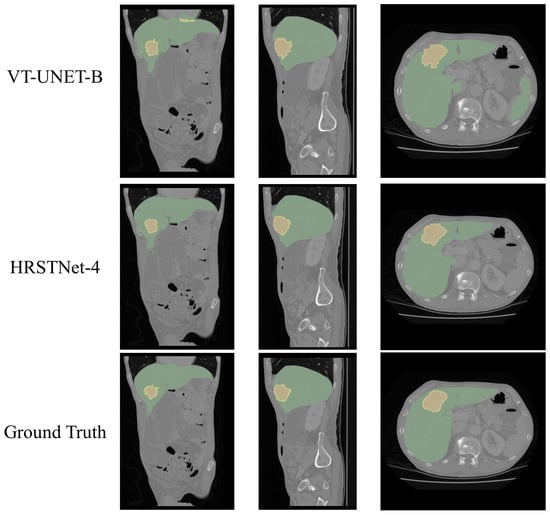

4.5. Experimental Results on the MSD Liver Dataset